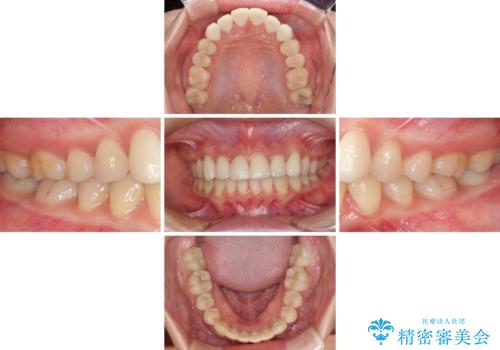

- コンポジットレジンによる治療で継ぎ接ぎだらけになってしまった前歯を綺麗にしたいとのことで来院された患者様です。

必要に応じて根管治療を行い、前歯6歯をオールセラミッククラウンで補綴することとしました。

治療途中に出産を迎えるため、下顎前歯のデコボコを部分矯正で改善し、上下前歯を綺麗に仕上げることとしました。

普段は海外在住であり、出産のための一時帰国を利用して短期集中治療を行いました。

自身の出産で大変な時期にもかかわらず、スケジュール通りに通院いただき、望まれたとおりの口元に仕上げることができました。